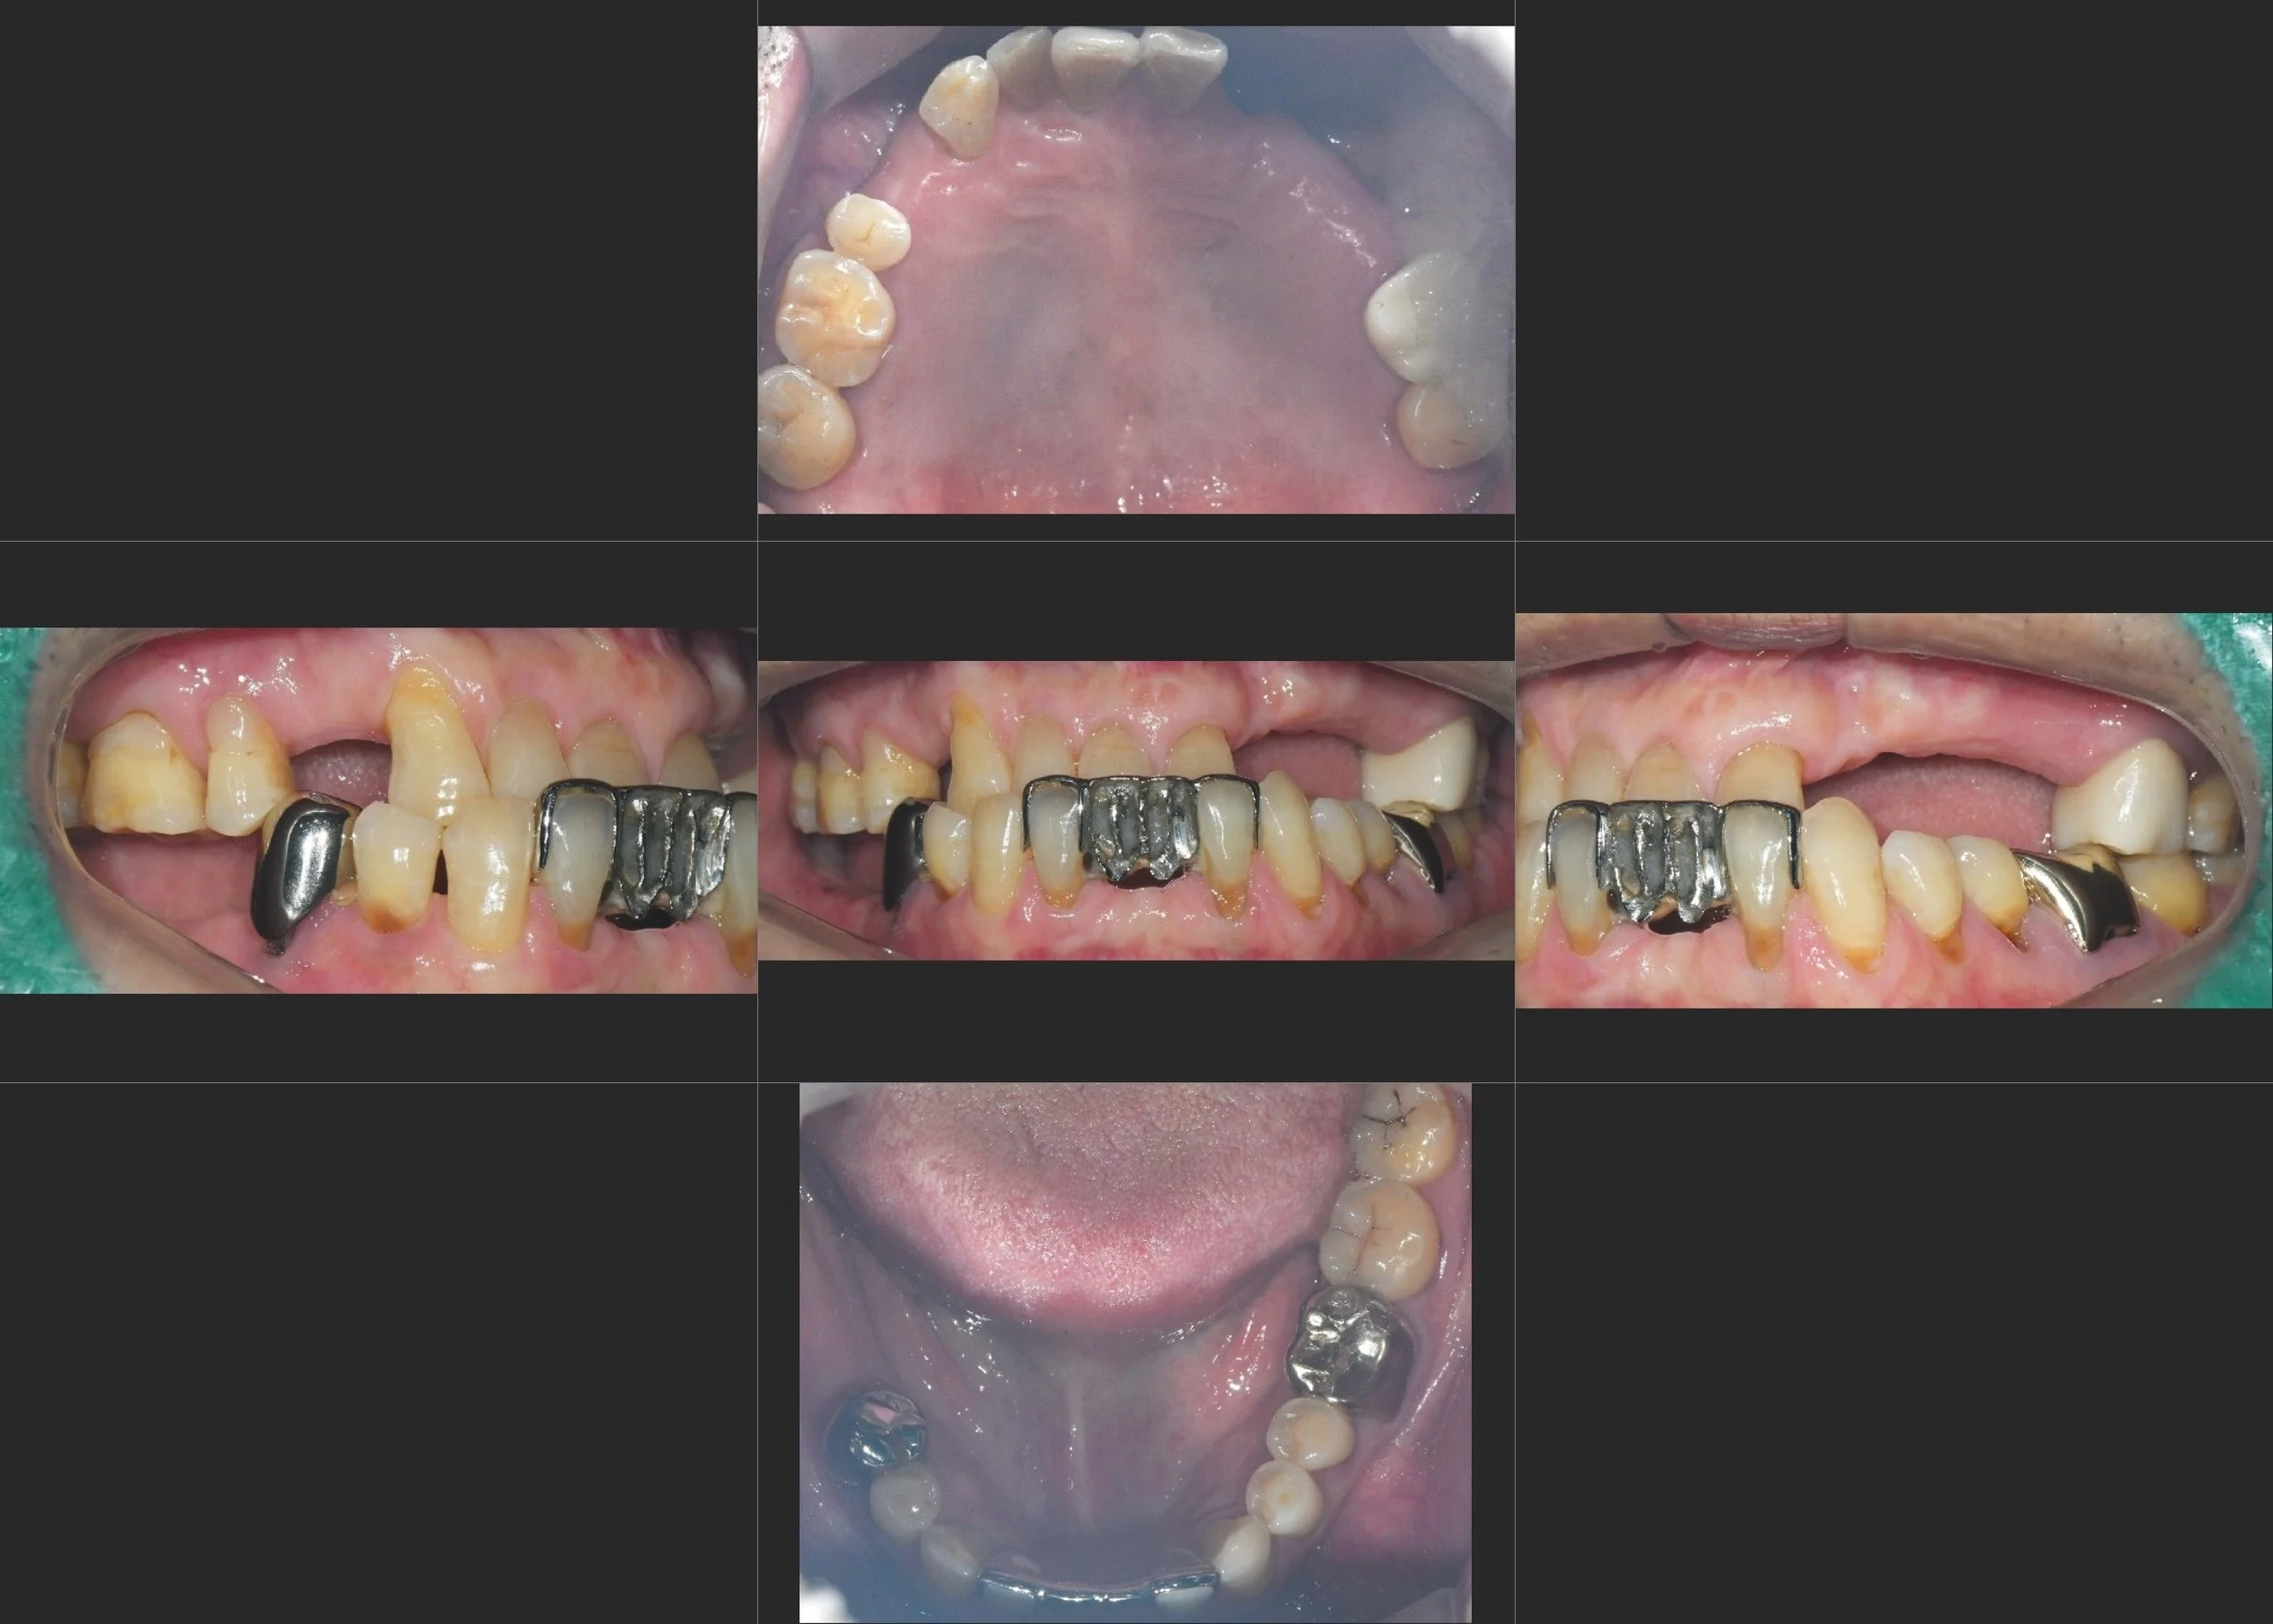

INTRA ORAL - BEFORE

A male patient in his 60s presented with a pronounced Class III skeletal relationship and a significantly collapsed facial profile. The loss of posterior occlusal height over time had caused the mandible to deviate further anteriorly, worsening the underbite and functional instability. The patient complained of reduced chewing efficiency and was highly dissatisfied with his "sunken" facial appearance.

• VDO Elevation: To recover the lost vertical dimension and create the necessary restorative space.

• Deviation Correction: To guide the mandible back from its pathological anterior-shifted position to a more neutral centric relation.

• Compromised Occlusion: To establish a stable and functional edge-to-edge bite relationship as a realistic clinical compromise for the skeletal Class III condition.